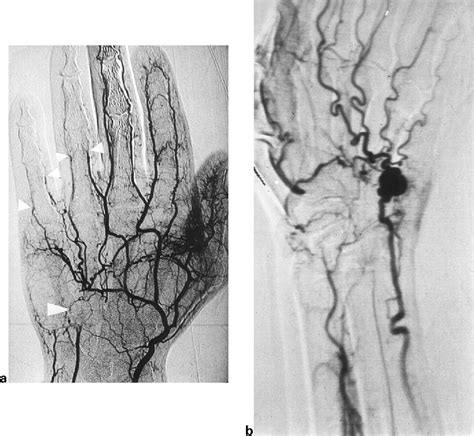

Correct diagnosis is paramount. Because the symptoms overlap with other vascular disorders, physicians usually employ a combination of clinical history and advanced imaging. A physical examination often includes the Allen’s test, which helps assess the patency of the ulnar and radial arteries. If HHS is suspected, the following diagnostic tools are typically utilized:

• Duplex Ultrasound: An excellent initial tool to visualize the blood flow and identify potential blockages or aneurysms.

• CT Angiography (CTA): Provides detailed imagery of the vascular anatomy and is highly effective at identifying aneurysms.

• Magnetic Resonance Angiography (MRA): A non-invasive method to evaluate the integrity of the arterial walls.

• Digital Subtraction Angiography (DSA): Considered the "gold standard" for definitive diagnosis, as it allows for real-time visualization of the blood flow within the hand.

• Aneurysm or Pseudoaneurysm: Weakening and bulging of the arterial wall, which may further lead to embolic events in the fingers.